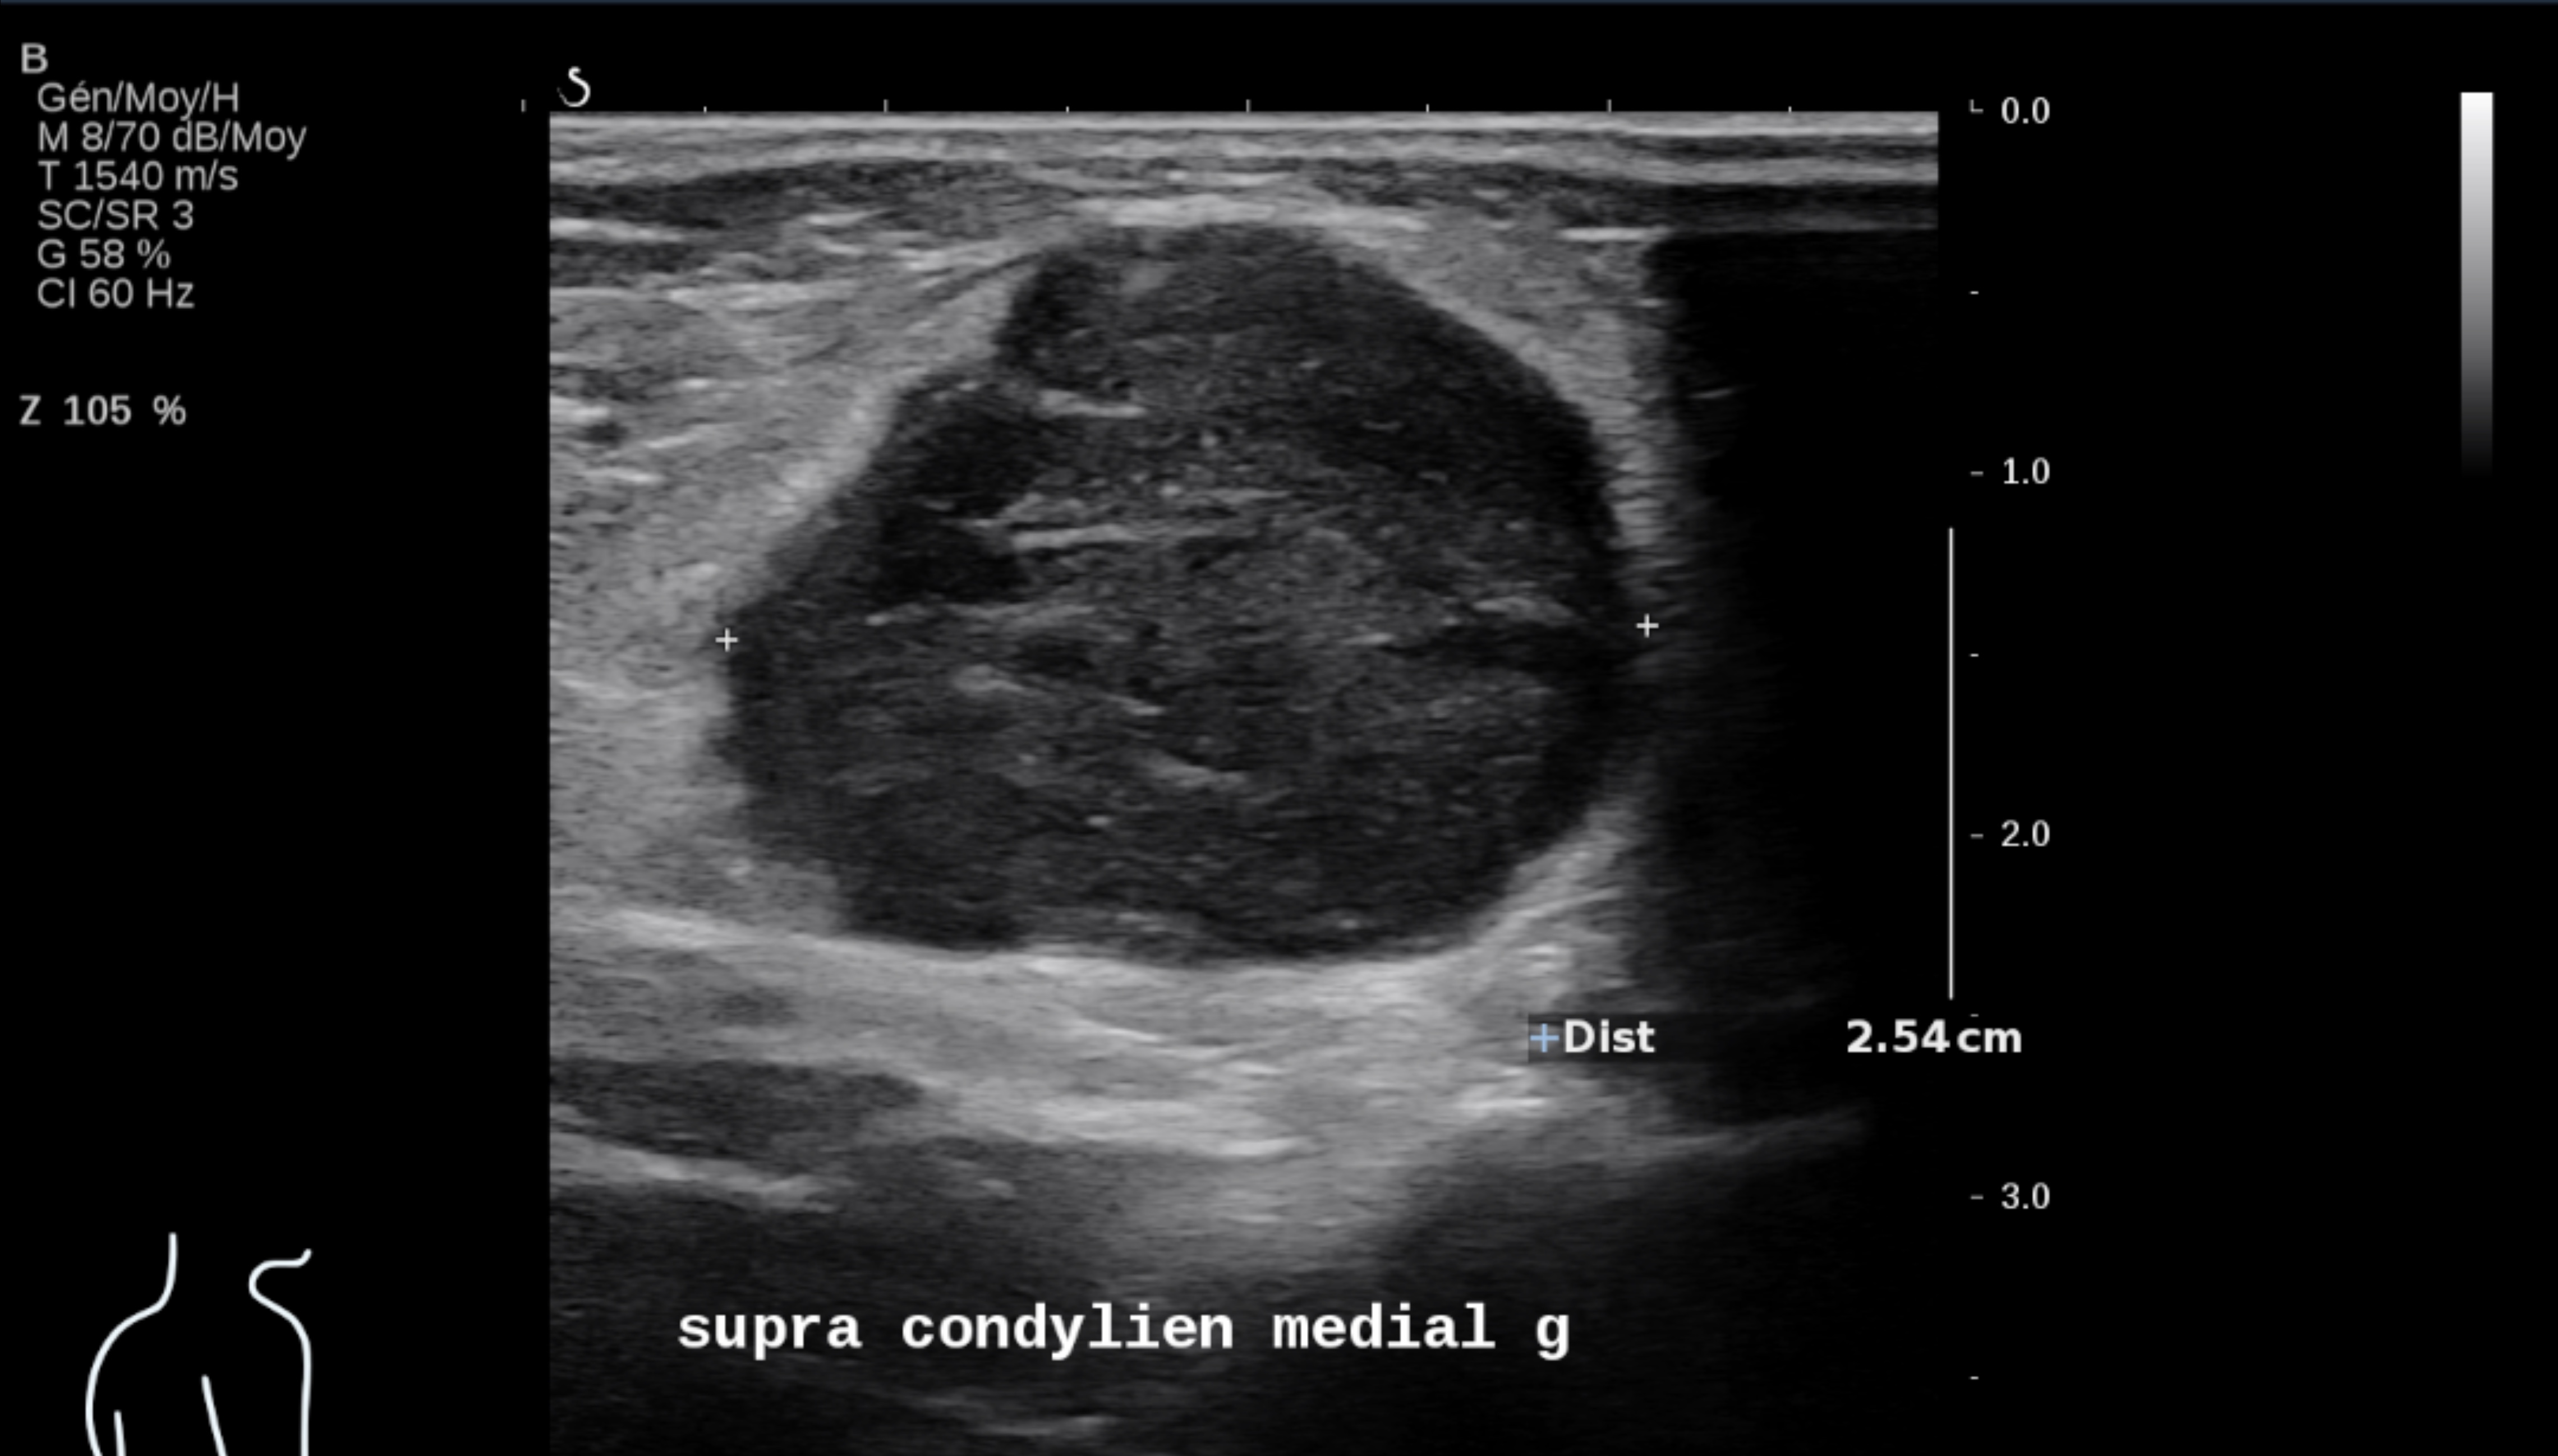

L’échographie reste le meilleur examen pour le suivi ganglionnaire superficiel et cutané des patients, à condition d’être réalisée par des opérateurs entraînés et spécialisés avec des appareils d’échographie performants utilisant des sondes de haute et très haute fréquence.